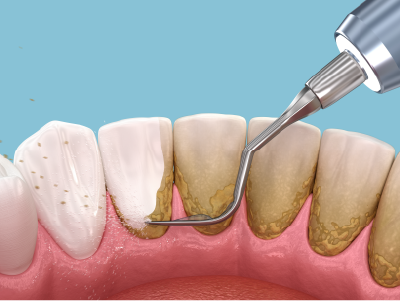

毎日の正しい歯磨きで、歯垢を徹底的に除去することが重要です。口腔内の細菌数を減らすのに第一歩となります。

歯茎の上の歯垢・歯石に対してはスケーリング、歯茎の下(歯周ポケット内)に入り込んだ歯垢・歯石に対してはルートプレーニングを行います。これにより歯の表面を滑らかにして、汚れが再付着しにくい環境を作ります。